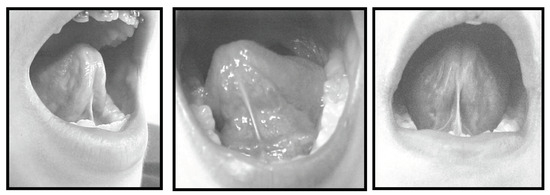

Following the classification of the frenulum as normal or altered, four measurements were obtained using the digital Starret slide caliper. All measurements were taken by a single speech therapist. The recorded measurements included: a) maximum mouth opening (with no tongue interference) as measured at the incisal edges of the left upper and lower central incisors. This measurement served as a reference support point for the slide caliper (Figure 4), and was taken as an absolute value reference for subsequent comparison with other measurements; b) for the second measurement each subject was requested to put the apex of his/her tongue on the palatine (incisal) papilla, maintaining this posture with the mouth open maximally and with the support points for the slide caliper maintained at the left central incisors (Figure 5); c) the third measurement was obtained while the subject created a negative pressure by sucking the tongue against the hard palate area, maintaining this position with the mouth open (Figure 6); d) the last measurement was taken while each subject protruded the tongue and stretched it maximally over a wooden spatula held by the examiner at the lower incisors (Figure 7). A mark made with a black pencil was recorded on the spatula at the place of the longest measurement of the tongue. Using the slide caliper, this measurement, from the tip of the spatula to the place where the tongue had reached in extension was measured (Figure 8). All measurements were logged onto a previously designed table consisting of the following data: initials of subject’s name and age, collection date, classification of frenulum as normal or altered, the measurements taken at full mouth opening, tongue on the papilla, tongue sucked against the hard palate, and tongue on the spatula. The rule of three was applied, comparing the wide-open mouth reference valus with each of the other three measurements. The data were collected between the months - August 2002 to December 2003.

Figure 7. Tongue on the Spatula.

Figure 8. Measuring the Spatula.